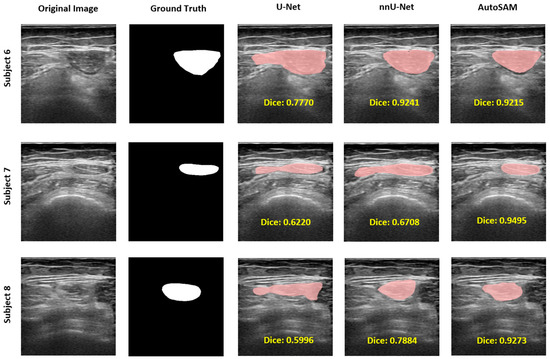

| Model | DICE | IoU | HD | Accuracy | Precision | Recall |

|---|---|---|---|---|---|---|

| U-Net | 0.8178 (SD = 0.1010) | 0.7035 (SD = 0.1371) | 4.2724 (SD = 2.6113) | 0.9637 (SD = 0.0175) | 0.9828 (SD = 0.0189)  | 0.9759 (SD = 0.0221)  |

| nnU-Net | 0.8910 (SD = 0.0610) | 0.8084 (SD = 0.0924) | 3.2074 (SD = 2.7506) | 0.9789 (SD = 0.0145) | 0.9881 (SD = 0.0143)  | 0.9884 (SD = 0.0142)  |

| Auto-SAM | 0.9205 (SD = 0.0449) | 0.8557 (SD = 0.0720) | 1.7213 (SD = 1.1670) | 0.9826 (SD = 0.0137) | 0.9897 (SD = 0.0109)  | 0.9911 (SD = 0.0141)  |